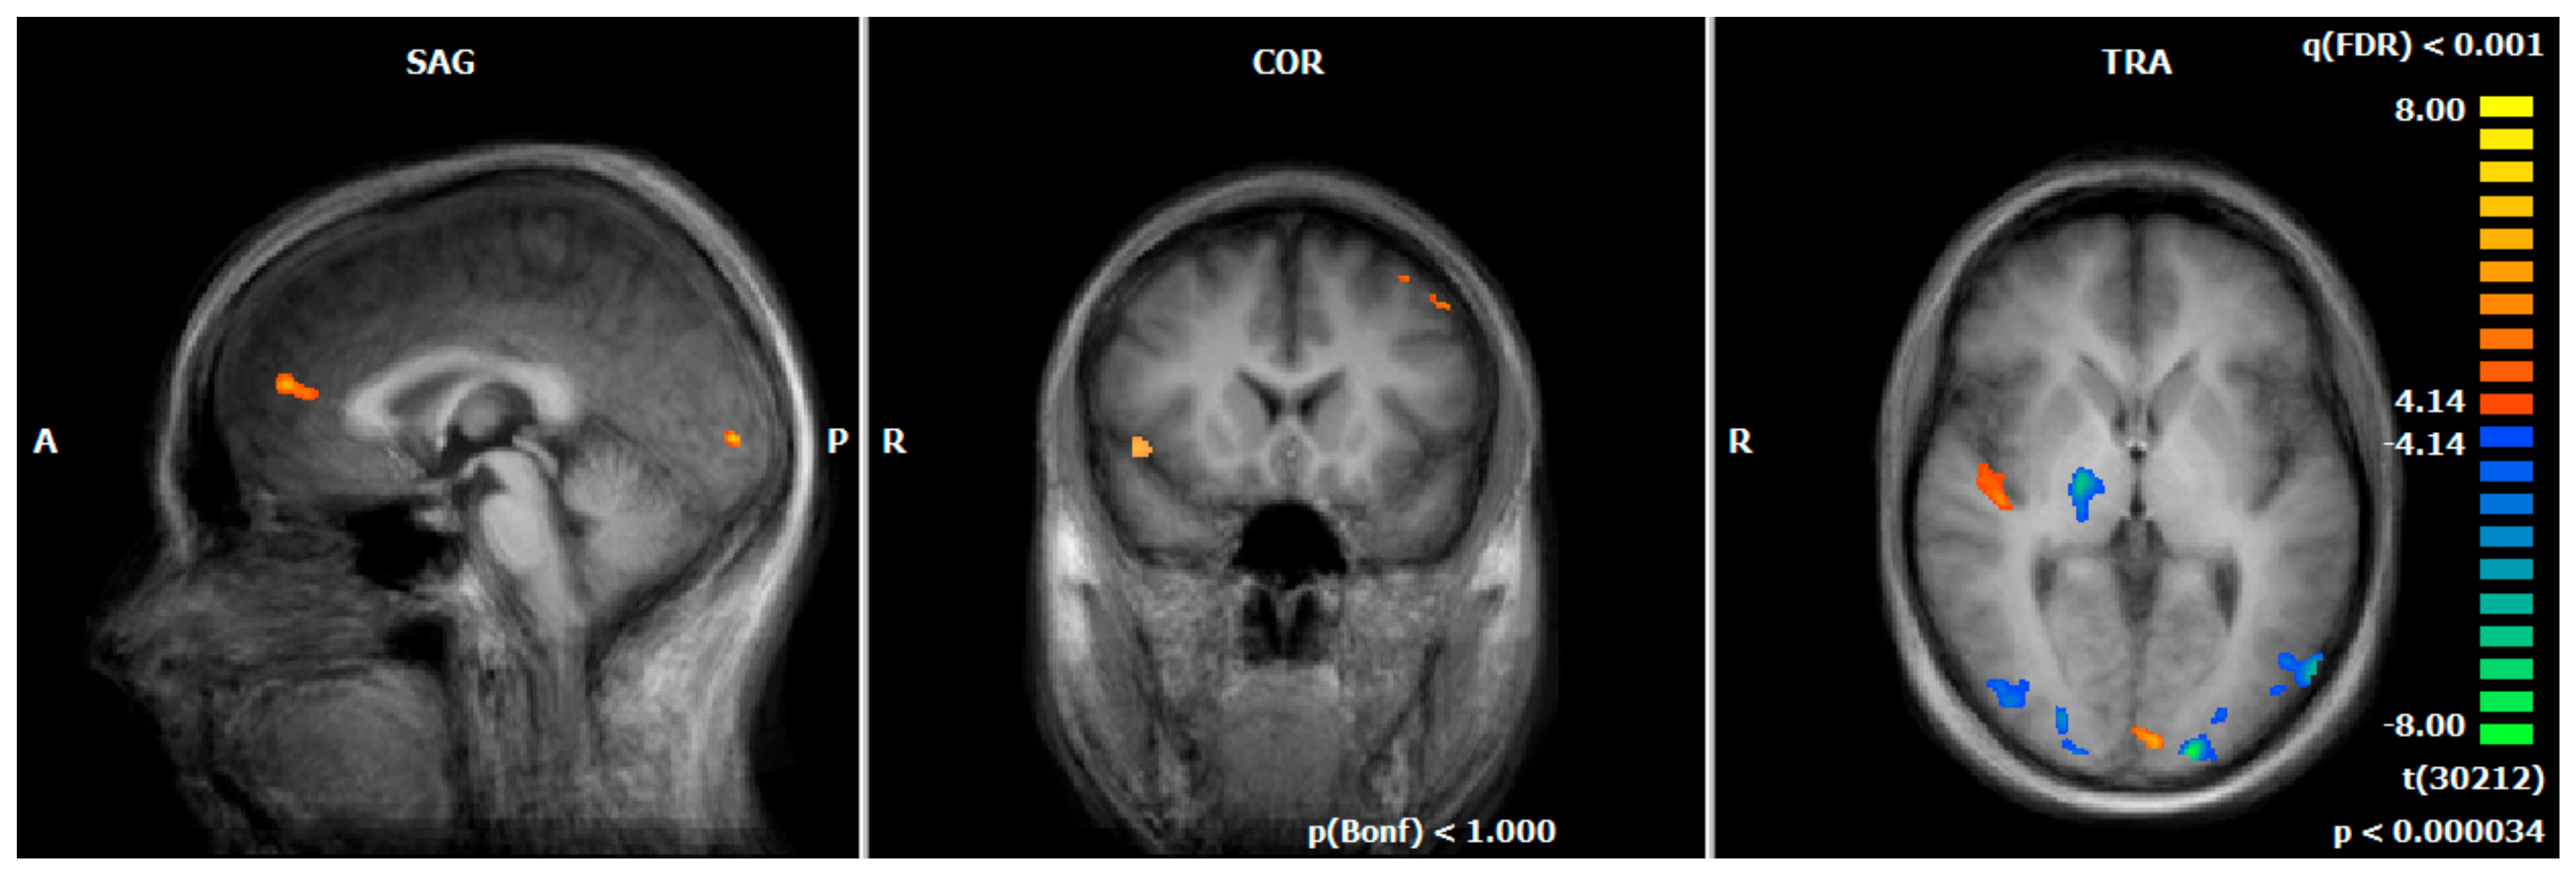

3.3. Hemodynamic Responses during the Emotion-Associated Task during the Functional Localizer on Day One: MDD REAL vs. HC REAL

| HC REAL > MDD REAL | ||||||||

| Middle Frontal Gyrus | L | 6 | −28 | −11 | 47 | 577 | 4.80 | 5.92 |

| Inferior Frontal Gyrus | R | 46 | 37 | 33 | 13 | 611 | 4.82 | 6.97 |

| Precentral Gyrus | L | 6 | −44 | 2 | 33 | 1118 | 4.77 | 5.99 |

| Thalamus | R | − | 16 | −14 | 3 | 655 | 5.13 | 7.12 |

| Cuneus | R | 17 | 21 | −88 | 6 | 419 | 5.11 | 6.86 |

| Middle Occipital Gyrus | R | 19 | 36 | −74 | 9 | 992 | 5.03 | 7.72 |

| Middle Occipital Gyrus | L | 19 | −36 | −76 | 5 | 3843 | 5.21 | 9.21 |

| MDD REAL > HC REAL | ||||||||

| Middle Frontal Gyrus | R | 8 | 30 | 21 | 46 | 665 | 4.80 | 6.56 |

| L | 8 | −33 | 18 | 48 | 476 | 4.82 | 5.95 | |

| Medial Frontal Gyrus | L | 9 | 0 | 45 | 17 | 260 | 4.99 | 6.86 |

| Thalamus | L | − | −9 | −31 | 15 | 482 | 4.75 | 6.22 |

| Postcentral Gyrus | R | 2 | 50 | −18 | 27 | 584 | 4.82 | 6.08 |

| Precentral Gyrus | R | 6 | 54 | −9 | 38 | 288 | 4.67 | 5.88 |

| Posterior Insula | R | 13 | 46 | −11 | 1 | 517 | 4.58 | 5.90 |

| Anterior Insula | R | 13 | 46 | 11 | −5 | 339 | 4.92 | 6.30 |

| Superior Temporal Gyrus | R | 22 | 36 | −57 | 21 | 251 | 4.76 | 6.09 |

| L | 41 | −52 | −27 | 16 | 244 | 4.84 | 6.38 | |

| Middle Temporal Gyrus | L | 39 | −40 | −51 | 9 | 644 | 4.56 | 5.63 |

| Supramarginal Gyrus | R | 40 | 56 | −345 | 22 | 275 | 5.10 | 6.97 |

| Lingual Gyrus | L | 17 | −4 | −90 | 2 | 267 | 5.46 | 8.02 |

| Cuneus | L | 18 | −8 | −71 | 18 | 265 | 4.59 | 5.40 |